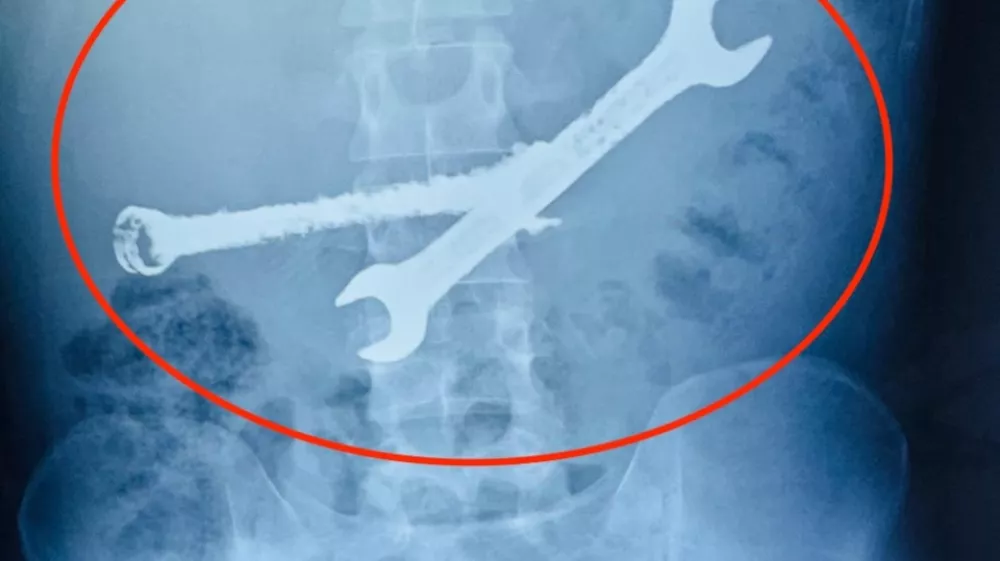

V želodcu 26-letnika so našli sedem zobnih ščetk in dva kovinska viličasta ključa. Foto: Profimedia

Zdravniška ekipa je v želodcu 26-letnika našla kar sedem zobnih ščetk in dva kovinska viličasta ključa. Ti predmeti so so bili v njegovem telesu več tednov. Zdravniki so predmete najprej poskušali odstraniti z endoskopijo, a so bili pri tem neuspešni. Zaradi resnosti stanja se je ekipa gastroenterologov odločila za nujno odprto operacijo, ki je trajala več kot dve uri, poroča Jutarnji list.

EXCLUSIVE: Story from Jam Press (Toothbrushes In Stomach)Pictured: A video grab of the doctors removing the seven toothbrushes and two spanners from inside the 26-year-old man's stomach.VIDEO: Tummy ache-suffering man leaves docs stunned as they find seven toothbrushes and two spanners in his stomachA tummy-ache-suffering man left doctors stunned after they found seven toothbrushes and two spanners in his stomach.They had been there for weeks.The 26-year-old was admitted to the hospital after complaining of chronic abdominal pain.Doctors were stunned to find multiple foreign objects inside his stomach.An endoscopy was attempted but failed to remove the objects.A senior gastroenterologist and his team then decided to proceed with open surgery.The operation lasted more than two hours in Jaipur, Rajasthan, India, as reported by What's The Jam.According to the doctors, the man's stomach was like a dustbin, and the objects could have been life-threatening.The patient from Bhilwara district was said to have a habit of swallowing iron tools and toothbrushes.He had swallowed these objects a month ago.But after the operation, his condition was described as stable.ENDSEDITOR'S NOTE: Video Usage Licence: (PROFESSIONAL PARTNER) We have obtained this material from a professional partner for use by our news media clients (company press release / other media agency).Video Restrictions: None.30 Dec 2025Pictured: Story from Jam Press (Toothbrushes In Stomach)Pictured: The seven toothbrushes and two spanners found inside the 26-year-old man's stomach.VIDEO: Tummy ache-suffering man leaves docs stunned as they find seven toothbrushes and two spanners in his stomachA tummy-ache-suffering man left doctors stunned after they found seven toothbrushes and two spanners in his stomach.They had been there for weeks.The 26-year-old was admitted to the hospital after complaining of chronic abdominal pain.Doctors were stunned to find multiple foreign objects inside his stomach.An endoscopy was attempted but failed to remove the objects.A senior gastroenterologist and his team then decided to proceed with open surgery.The operation lasted more than two hours in Jaipur, Rajasthan, India, as reported by What's The Jam.According to the doctors, the man's stomach was like a dustbin, and the objects could have been life-threatening.The patient from Bhilwara district was said to have a habit.,Image: 1062304669, License: Rights-managed, Restrictions: NO Australia, Germany, Norway, South Korea, Sweden, United Kingdom, United States, Unknown Country, Model Release: no